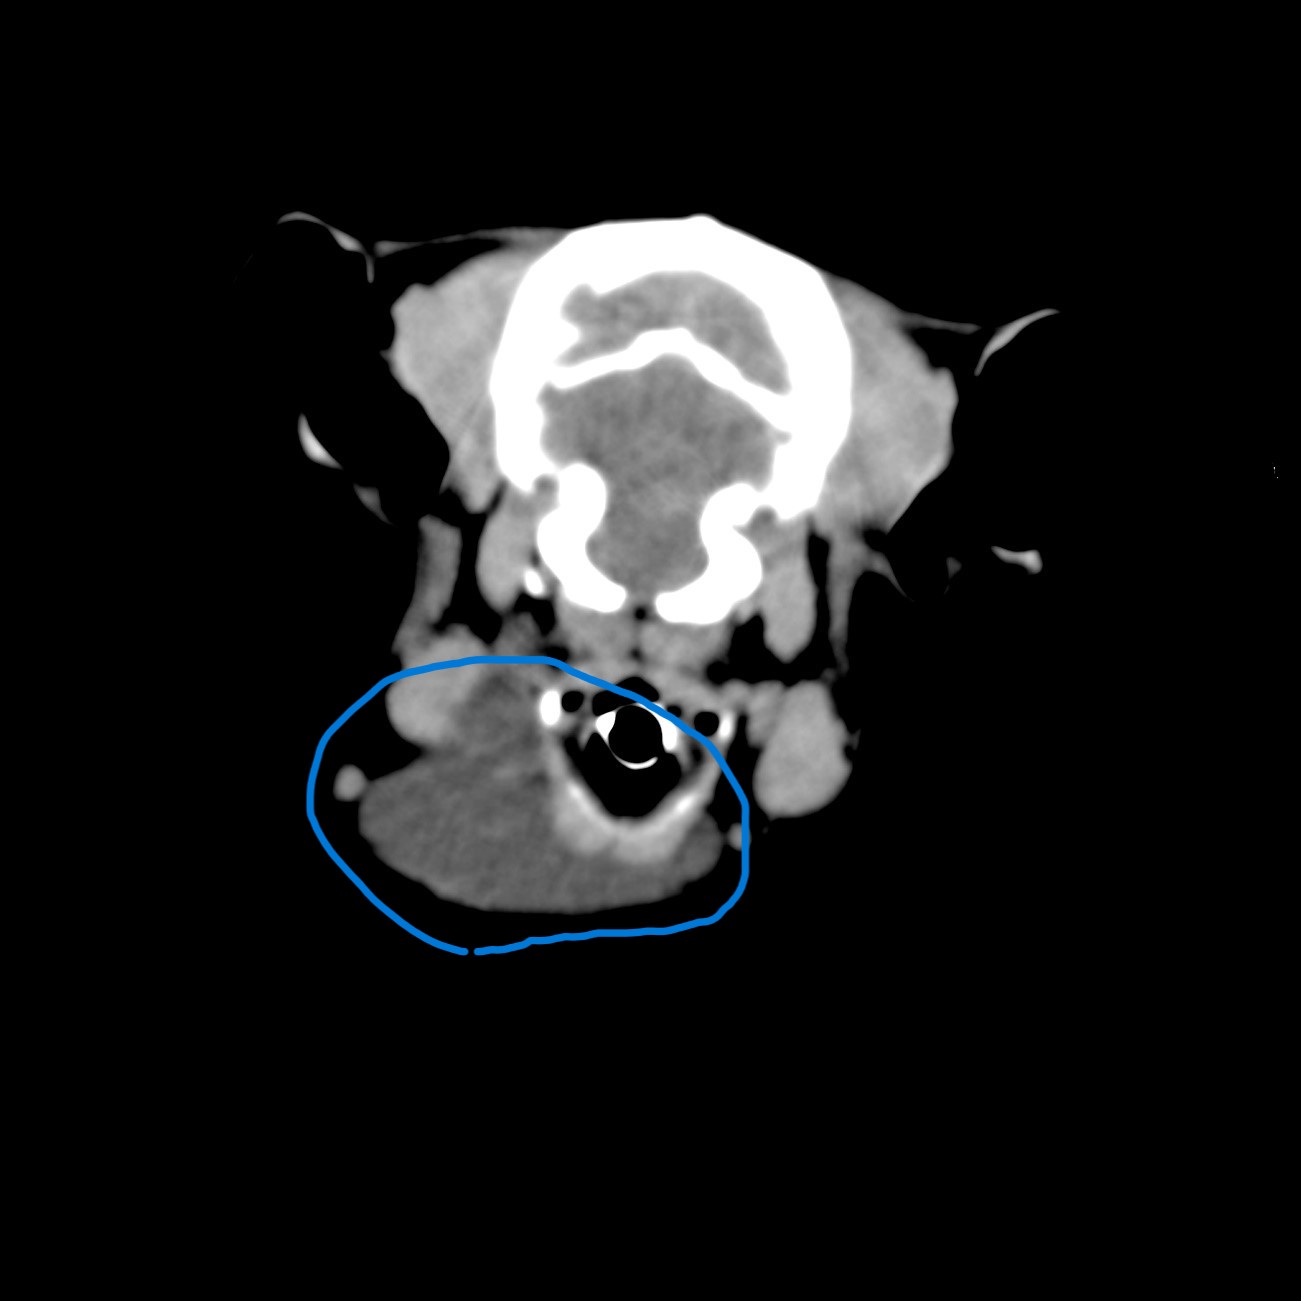

8歳トイプードル去勢雄、体重3.0kg。3日前からのどの部分が腫れているとの主訴で受診されました。

直径5㎝ほどの波動感のある腫瘤があり、痛みや他の症状はありませんでした。レントゲン検査では頭頸部の骨組織や頸部腫瘤周囲の軟部組織に異常は見られませんでした。針吸引を試みたところ半透明の粘稠性の唾液が採集されました。

また、腫瘍などの鑑別診断と外科手術の検討のためCT検査を行いました。結果は腫瘍や唾石は認められませんでした。

丸で囲んだ部分が唾液瘤